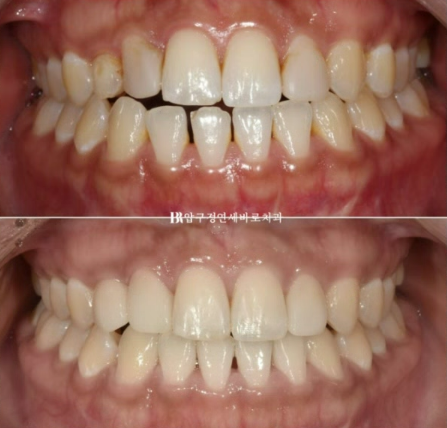

23.02~23.08

좌우 사이즈가 달랐던 부분을 교정으로 적절히 공간분배를 했기 때문에 동일한 사이즈와 라미네이트가 각각 들어갈수 있었습니다.

삭제 없이 라미네이트가 들어간 모습입니다.

가운데 앞니 두개는 본래 치아이고 파란 화살표 부분만 무삭제 라미네이트입니다.

23.08